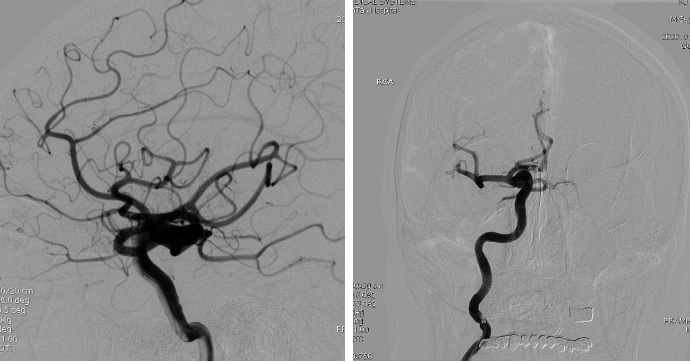

全脑血管造影:右侧大脑中动脉M1分叉处动脉瘤,瘤体3.3 mm*4.1 mm,瘤颈2.7 mm。前交通动脉瘤栓塞完全。

全麻满意后,常规消毒铺巾,采用改良 Seldinger技术穿刺右侧股动脉成功,置入6F动脉鞘。黑泥鳅导丝带领5F单弯导管行脑动脉造影,右侧颈内动脉造影见:右侧大脑中动脉M1分叉处动脉瘤,瘤体3.3 mm*4.1 mm,瘤颈2.7 mm。前交通动脉瘤栓塞完全。

经右侧股动脉鞘,黑泥鳅导丝带领导引导管(Codman 6F Envoy DA)到达右侧颈内动脉岩段,微导丝(Synchro--14 0.014 in*200 cm)带领支架微导管(Excelsior SL--10)到达右侧大脑中动脉M2段,退出微导丝。微导丝带领弹簧圈微导管(Echelon10)到达右侧M1远端分叉处动脉瘤内,退出微导丝。经弹簧圈微导管填入弹簧圈(Codman 3 mm*4 cm)经支架微导管输送支架(Neuroform Atlas 3.0 mm*15 mm)并释放在M2段至M段中部,完全覆盖动脉瘤颈。继续经弹簧圈微导管依次填入弹簧圈数枚,间断造影确保右侧大脑中动脉及远端血流通畅。右侧颈内动脉造影确认:动脉瘤致密填塞,载瘤动脉通畅,手术结束。有侧股动脉穿刺处用血管封堵器封堵,并压迫器持续压迫。术后患者麻醉清醒,拔除气管插管,呼唤应答,对答切题,言语清楚,四肢肌力肌张力正常。安返病房。